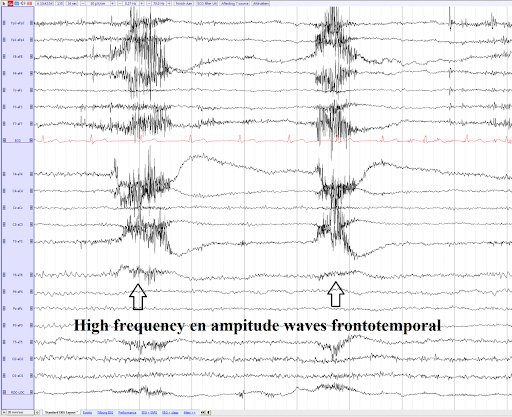

- Also, though there is filteration, some signals from eyes and muscle movements can affect the data, as well as oil and hair between the electrodes can weaken the connection.

This shows how muscle movements and eye blinks can affect EEG data, potentially give inaccurate results.